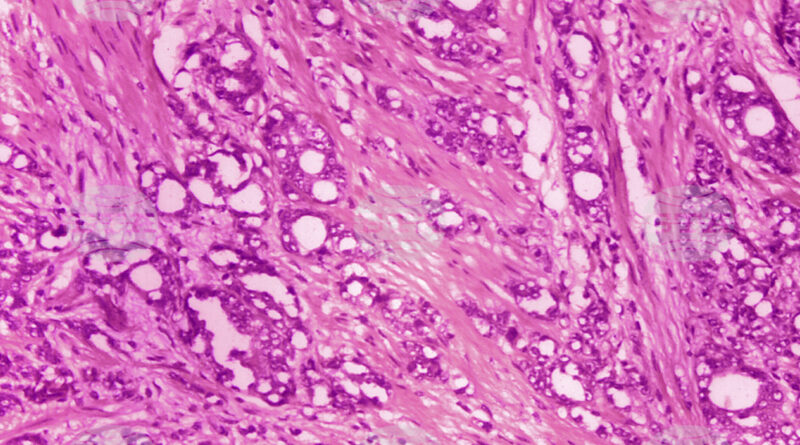

В експерименти с мишки с рак на пикочния мехур подобно доставяне е довело до намаляване на масата на туморите с около 60 процента за 21 дни, което е значително по-ефективно, отколкото при въвеждането на същото лекарство без микророботи.